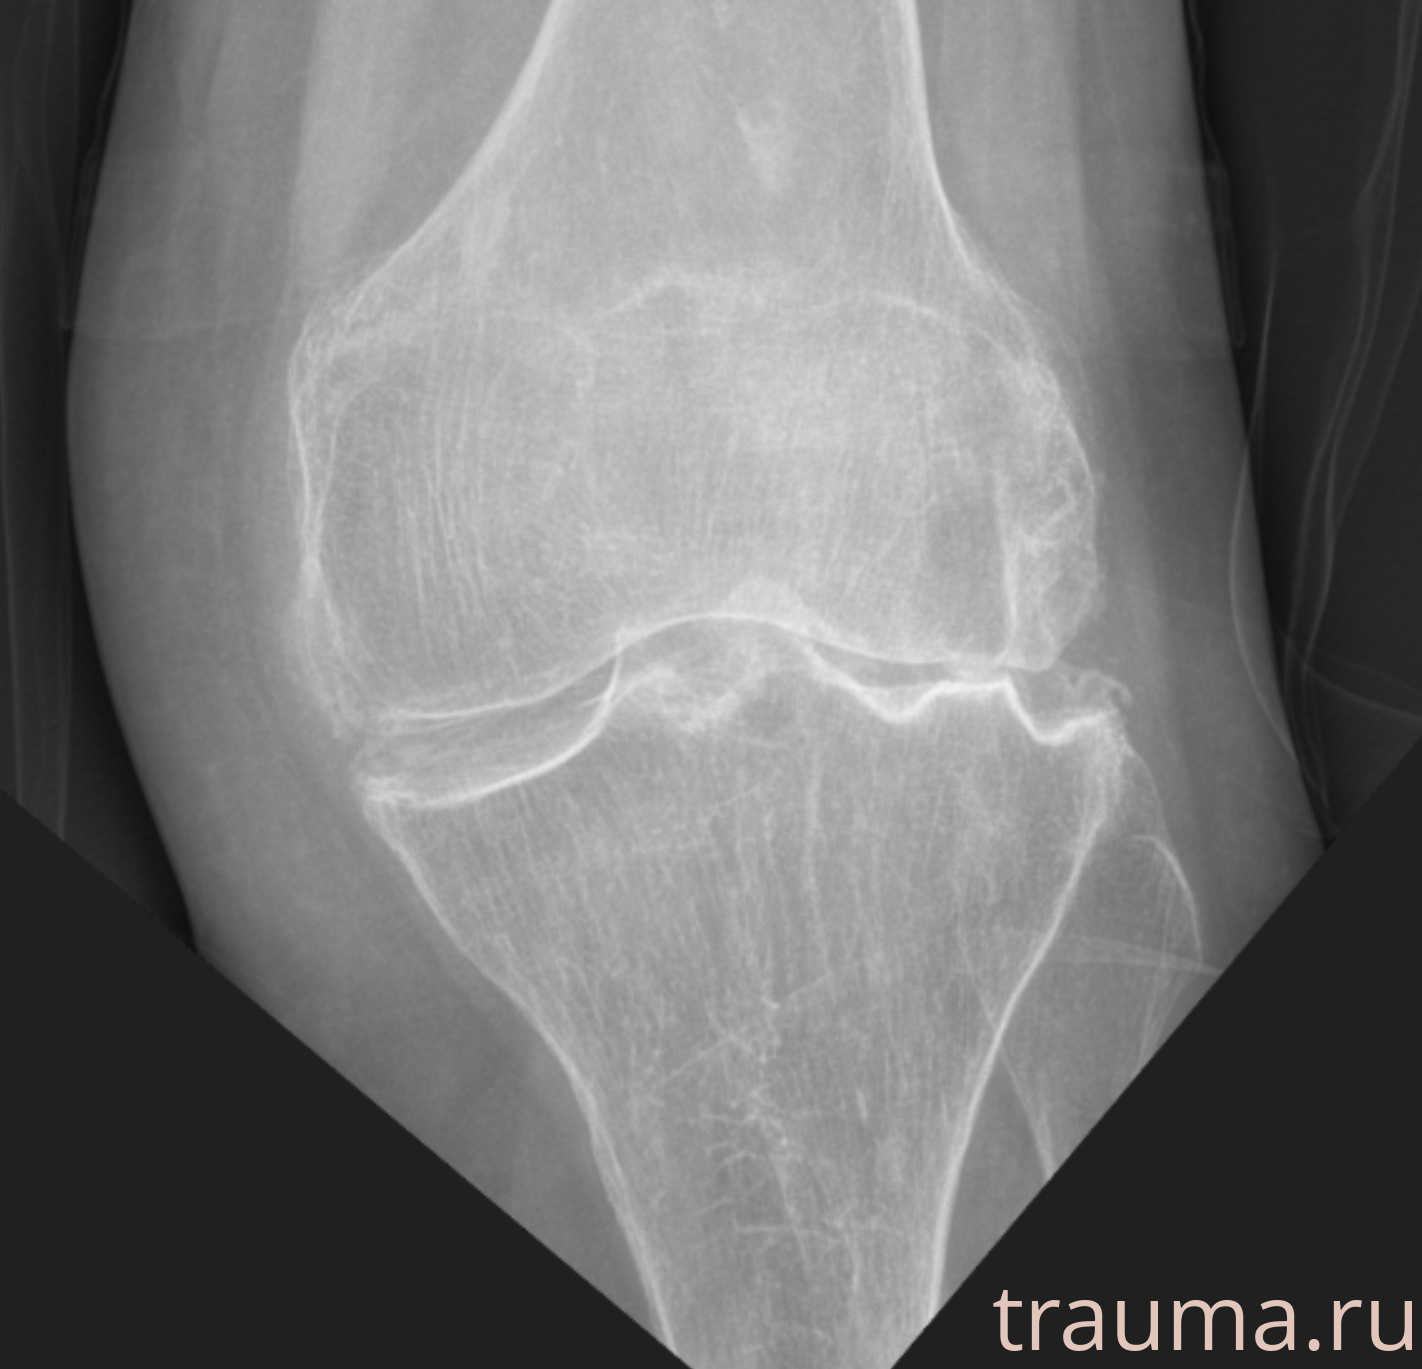

Рентген на дому: по вашему адресу приезжает врач-рентгенолог, травматолог-ортопед с мобильным рентгеновским аппаратом, проводит диагностику травмы или заболевания, делает необходимые рентгенограммы, дает рекомендации по дальнейшему лечению. Получить качественные снимки в домашних условиях возможно благодаря уникальной методике, разработанной МосРентген Центром для института  Склифосовского